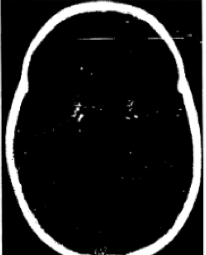

Anak dengan HIV-positif menunjukkan regresi perkembangan engan pelemahan motorik dan kognitif dengan kombinasi tanda piramidal dan sereberal, gambar ini adalah CT kepala pasien. apakah implikasi dari temuan pada CT tersebut?

A. Basal Ganglia Calcification seen in some children with HPE

B. Basal Ganglia Calcification as an Incidental finding to HPE

C. Calcification due to toxoplasmosis

D. Hemorrhage

A